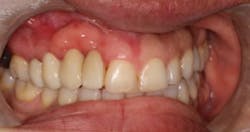

This patient presented with a long-standing edentulous area in the site of Nos. 6 and 7. She had lost both hard- and soft-tissue volume in the vertical and horizontal dimensions (figures 7 and 7a). Implant therapy was discussed as well as the option of multiple ridge augmentation procedures versus gingival ceramics. Although the patient has a low smile line, she was adamant about attempting to achieve a more proportional tooth length at final restoration. In addition, she complained about sensitive tissue underneath the pontic areas and an inability to clean her prosthesis. The periodontist and the patient decided to attempt to rebuild bony hard tissue and keratinized soft tissue. The patient understood the increase in finances and surgical procedures that would be involved.

The patient was referred to a periodontist who first augmented the edentulous site with a hard-tissue graft and membrane (figures 8 and 8a). Six months later, implants were placed in ideal positon (figure 9).

At the time of Stage II, six months after implant placement, a palatal roll soft-tissue augmentation was performed (figures 10 and 10a). Six weeks later, the area was provisionalized with new temporaries to develop soft tissue.

Two years after the patient first presented with her edentulous site, the case was completed and the patient was extremely happy (figures 11 and 11a).